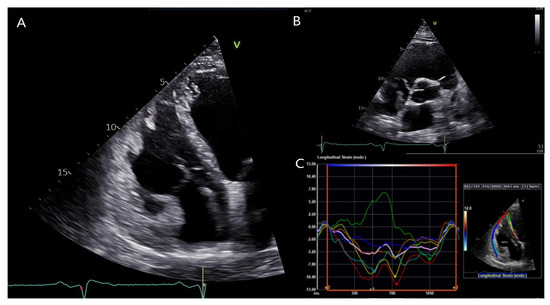

2. Case Description

3. Diagnostic Assessment